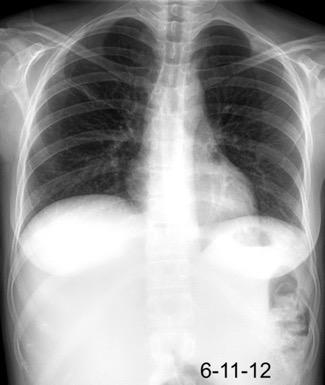

Accidente de tráfico

Rx: Niveles hidroaéreos en hemitórax izquierdo Desviación mediastínica Ausencia de intestino en abdomen. Configuración en reloj de arena del intestino herniado “Tubo nasogástrico”

Furak J et al. Diaphragm and transdiaphragmatic injuries. J Thorac Dis 2019